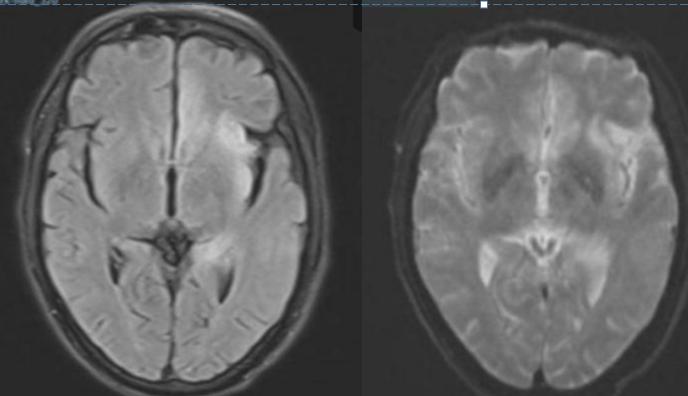

男性59岁,主因头痛发热9天,认知下降5天入院。查体:神志清,反应迟钝,记忆力下降,定向力和计算力检查不合作,肌力和肌张力基本正常。

答案:单纯疱疹病毒性脑炎。复查后如下:

单纯疱疹病毒性脑炎(HSE)是由单纯疱疹病毒(herpessimplexvirus,HSV)感染引起的一种急性CNS感染性疾病,又称为急性坏死性脑炎。HSV有两种血清型,即HSV-1和HSV-2。在人类大约90%HSE由HSV-1引起。仅10%由HSV-2所致,且HSV-2所引起的HSE主要发生在新生儿,是新生儿通过产道时被HSV-2感染所致。神经节中的神经细胞是病毒潜伏的主要场所,HSV-1主要潜伏在三叉神经节,HSV-2潜伏在骶神经节。当人体受到各种非特异性刺激使机体免疫力下降,潜伏的病毒再度活化,通过嗅神经和三叉神经侵入脑策划,常选择性损害额叶基底部和颞叶,不损害豆状核。临床常见症状有:头痛、呕吐、轻微的意识和人格改变、记忆丧失、轻偏瘫、偏盲、失语、共济失调、癫痫发作、多动(震颤、舞蹈样动作、肌阵挛)、脑膜刺激征等。精神行为异常可为首发或唯一症状。单疱病毒性脑炎MR表现以双侧颞叶、额叶受累为主,脑岛及海马均受累,病变均与豆状核分界清楚,以外囊为界。